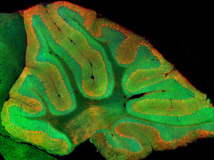

El equipo de Stanford ha utilizado una técnica nueva para observar en directo las células granulosas, conocida como microscopía de excitación de dos fotones. Es una técnica de proyección de imagen fluorescente que permite la imagen de tejido vivo hasta una profundidad de un milímetro.

El resultado de esta técnica permite observar la imagen de un órgano con una coloración verde que no es un color falso, sino una sustancia conocida como proteína verde fluorescente. En realidad es una proteína producida por la medusa Aequorea victoria, que emite fluorescencia en la zona verde del espectro visible. El gen que codifica esta proteína está aislado y se utiliza habitualmente en biología molecular como marcador.

Dada esta propiedad de la proteína verde fluorescente de destacar sobre otras, los investigadores la introdujeron mediante manipulación genética en el ADN de los ratones del experimento, con la finalidad de observar en vivo y en directo el funcionamiento de las células granulosas del cerebelo de los ratones en acción.